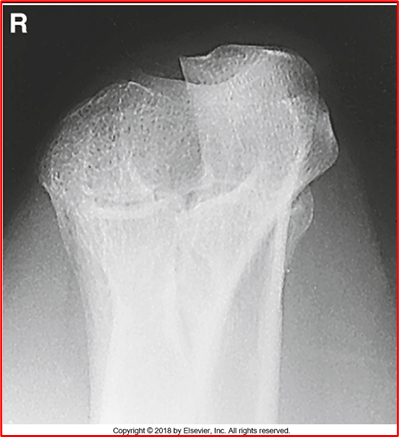

-Radius and ulna should be completely separated (almost there but not fully)

-There is crowning of the radial head (should NOT be present, should be flat) meaning they are not fully extended

-Capitulum and radial head present

-REPEAT because of crowning

critique this lateral oblique elbow image